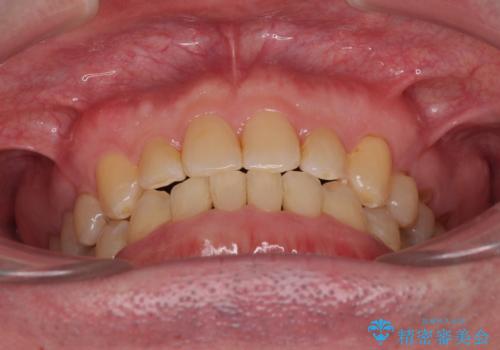

受け口を治す ワイヤー装置での矯正治療

- 上下前歯の反対咬合と左下奥歯の痛みを気にして来院された患者様です。

歯並びや口元の印象、奥歯の咬み合わせから、非抜歯にて矯正治療を行うこととしました。

インプラント埋入による仮歯の装着や、前歯の反対咬合の改善は比較的スムーズに達成されましたが、舌突出癖などの影響による、歯列全体のスペースを閉じることが難航し、期間がかかってしまいました。

治療後も舌突出癖が残っていると、あっという間にスペースができてしまうので、トレーニングを継続するように指導をしています。